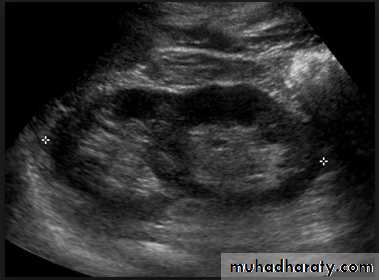

Adult typePresent after the third decade of life , Familial.

Renal parenchyma is replaced by numerous cysts containing fluid , The cysts are of variable size ,

Clinically renal colic, loin mass , heamaturia and hypertension, Renal tissue interposed between the cysts after time dssimcted ended with renal failure

Almost bilateral.